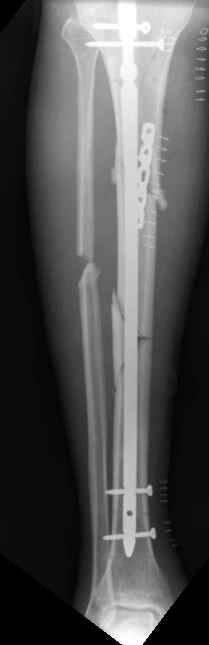

1

2

These can be challenging. I agree w/ all Dr. Carr's points. My preference to prevent the deformity is to use an anteromedial plate. See attached case.